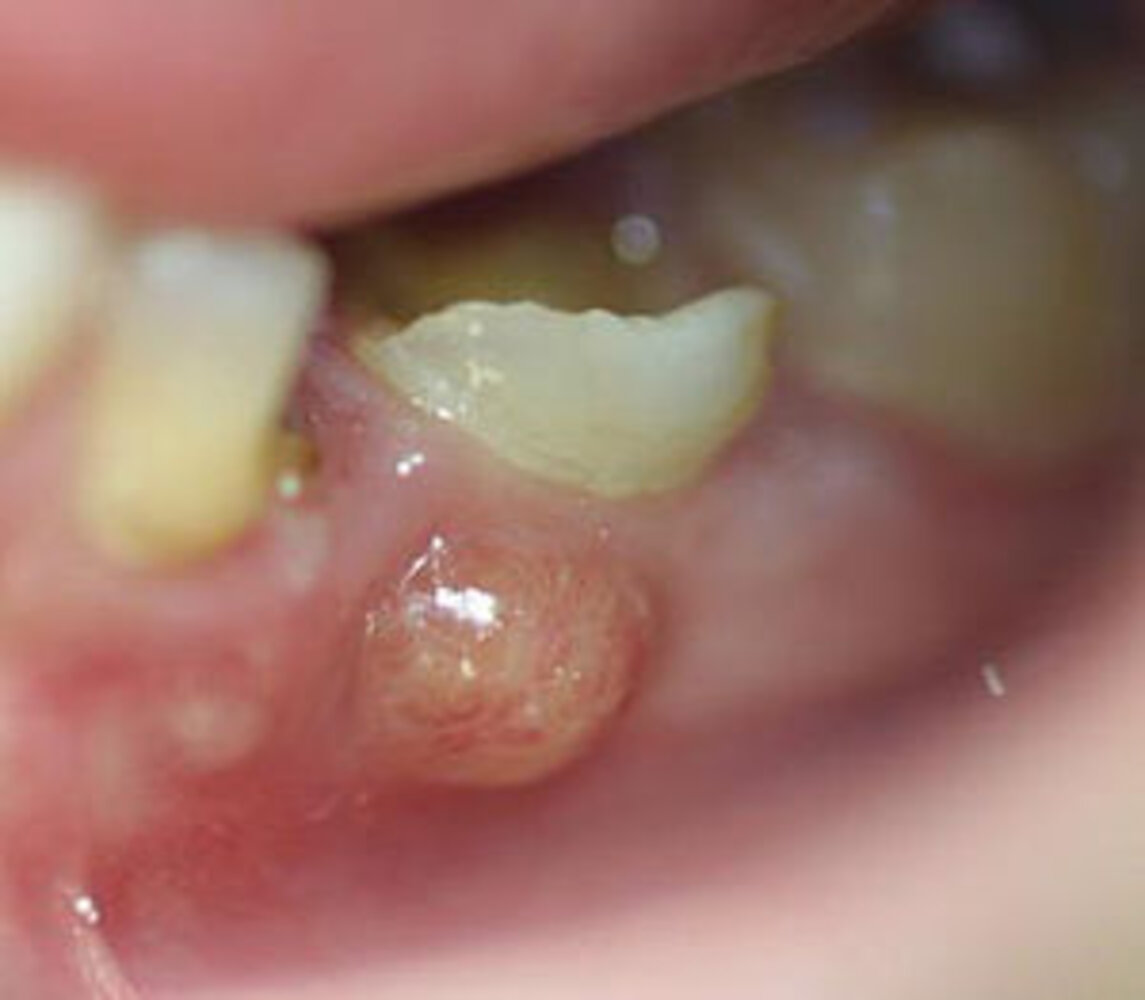

Overview

• Definition: the accumulation of purulent fluid within the dental pulp or periodontal tissue [10]

• Types [4]

• Periapical abscess

• Most common type

• Tooth decay or trauma → bacterial infection in the pulp of the tooth → collection of pus at the apex of the dental root

• The infection becomes visible when it extends through the alveolar bone (e.g., via a fistula) to the surrounding tissue. [11]

• Periodontal abscess

• Second most common type

• Periodontitis or impaction of foreign objects (e.g., food, dental floss) → bacterial infection deep in the periodontal pocket → collection of pus between the teeth and gingiva

• The affected tooth may be mobile.

Clinical features

• Severe pain can generally be elicited with palpation.

• Swelling and erythema of the surrounding mucosa

• Purulent discharge from the gum line may be seen.

• The affected tooth may be discolored and/or show enamel breaks.